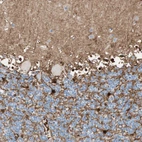

Immunohistochemistry analysis in human cerebral cortex and kidney tissues using HPA007316 antibody. Corresponding GLUL RNA-seq data are presented for the same tissues.